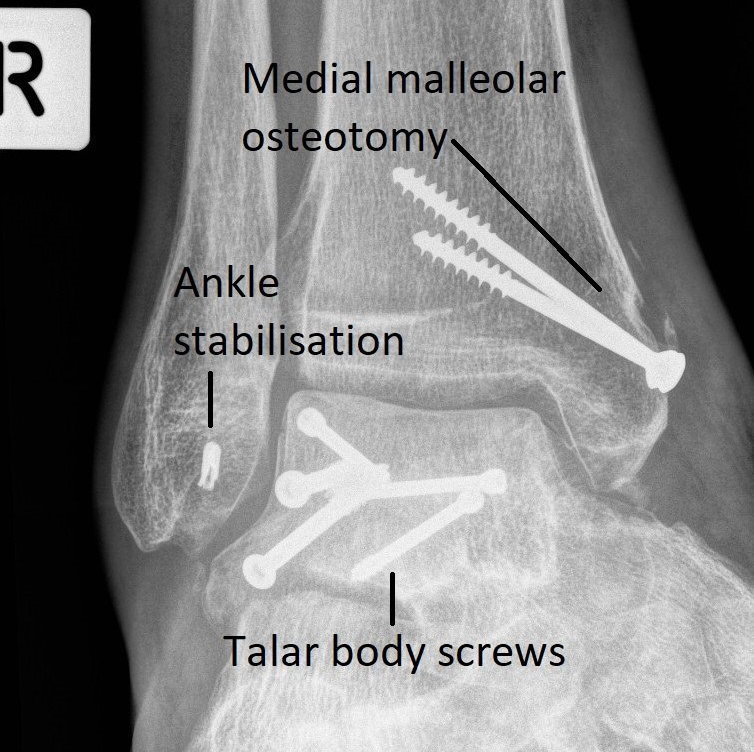

- X-rays (see image)

These imaging investigations show which part of the talus is broken and how badly. This determines both the need for surgery and the risk of long-term complications. These injuries can lead to severe ankle and hindfoot osteo-arthritis.

Talar fractures can involve the head, neck, body or processes of the talus.

- Surgical Treatment: If the fractured bones have shifted out of position, surgery to realign and stabilize the talus with metal screws and/or plates is required. After surgery, people need to use crutches and wear a "moon-boot" for 8 - 12 weeks. Physiotherapy is required to restore movement.